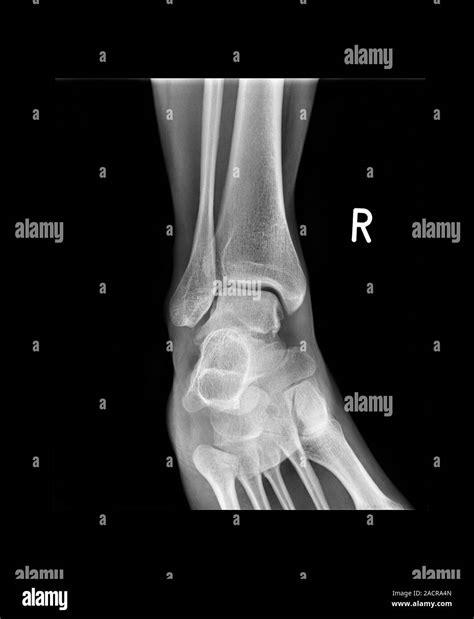

To determine the severity of a shattered talus bone, orthopedic surgeons rely on high-resolution imaging. Standard X-rays provide the initial view, but they are rarely enough to see the full extent of a comminuted fracture. A CT scan is almost always required to map out the fragments in 3D, allowing the surgeon to plan the reconstruction. MRI scans may also be used to evaluate the health of the soft tissues and the status of the blood supply to the bone fragments.

X-Ray Initial assessment of major displacements.

CT Scan Detailed mapping of bone fragments and joint surface damage.

MRI Evaluating ligament damage and blood flow status.